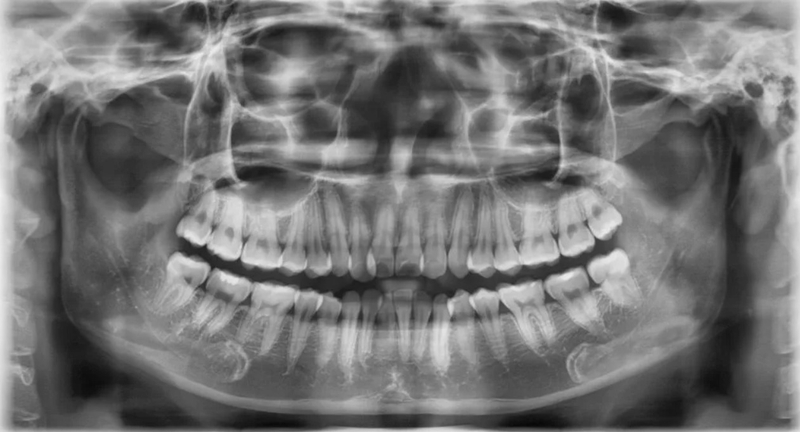

Tia X hỗ trợ phát hiện các vấn đề về răng hàm mặt bao gồm: